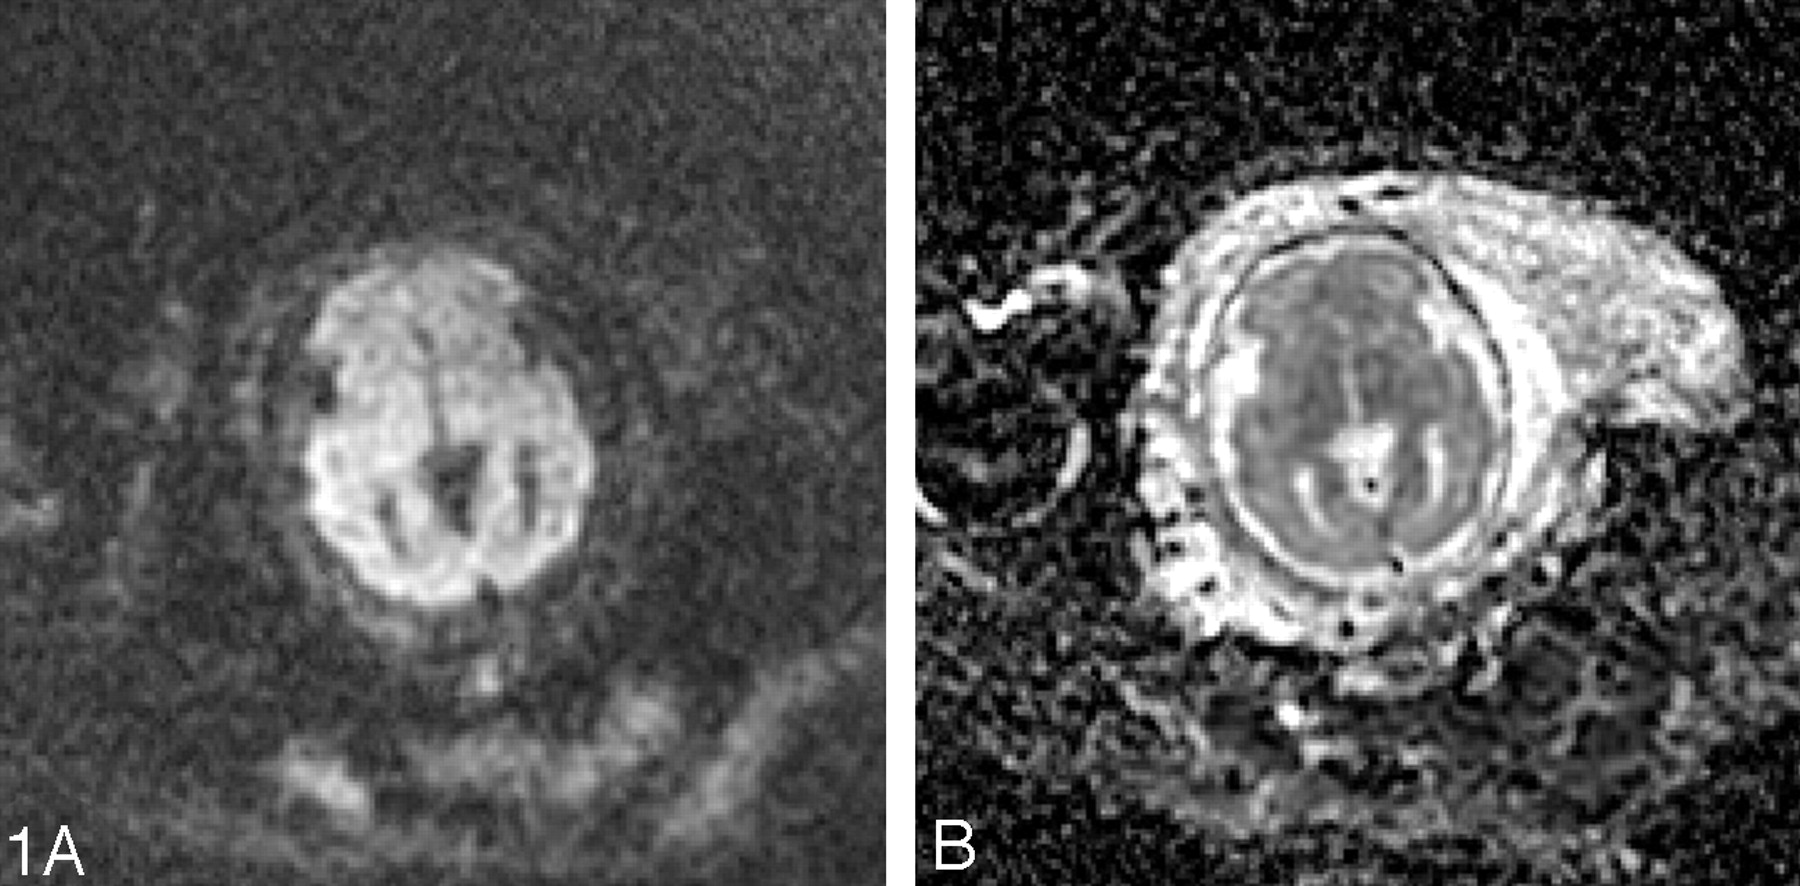

Advanced MR techniques, such as diffusion-weighted imaging, spectroscopy, and parallel imaging, have also recently been successfully applied to fetal MR imaging, though their development is still in the early stages. Diffusion-weighted imaging provides quantitative information about water motion and tissue microstructure. Fetal diffusion-weighted imaging has applications for both developmental and destructive brain processes. Single-shot, echo-planar, diffusion-weighted images are acquired in 18 seconds during a single maternal breath hold (Fig 1). Scanning parameters include TR = 4500 ms, TE = minimum, field of view = 32 cm, matrix = 128 × 128, section thickness = 5 mm, intersection gap = 2 mm, and bandwidth = 167 kHz. Gradients are applied in 3 orthogonal directions using a b-value of 0 and 600 seconds/mm2. Because of the relatively long scan time, images are susceptible to both fetal and maternal motion. With increasing gestational age and engagement of fetal head in the pelvis, the amount of motion is decreased and the quality of the studies improves. Diffusion-tensor imaging (DTI) has recently been applied to fetal autopsy specimens.29 Although its application to living fetuses is currently not feasible because of long acquisition times, progress is being made in this direction.30 Because of the long acquisition time (4.5 minutes) and size of the voxel relative to the fetal brain size, MR spectroscopy is limited to application in the third trimester when the fetal head is relatively large and engaged in the pelvis. Shorter acquisition times can be used but are limited by signal intensity-to-noise ratio.31 Normal metabolites such as N-acetylaspartate, creatine, and choline can be detected.32,33 Parallel imaging can also be applied to fetal MR imaging to decrease the scan time, increase image resolution, or decrease specific absorption rate.

A, Diffusion-weighted image at the level of the deep gray nuclei in a 29-week-old fetus is free of motion artifact.

B, Corresponding apparent diffusion coefficient map shows lower apparent diffusion coefficient (ADC) values in the developing cortex compared with the developing white matter.